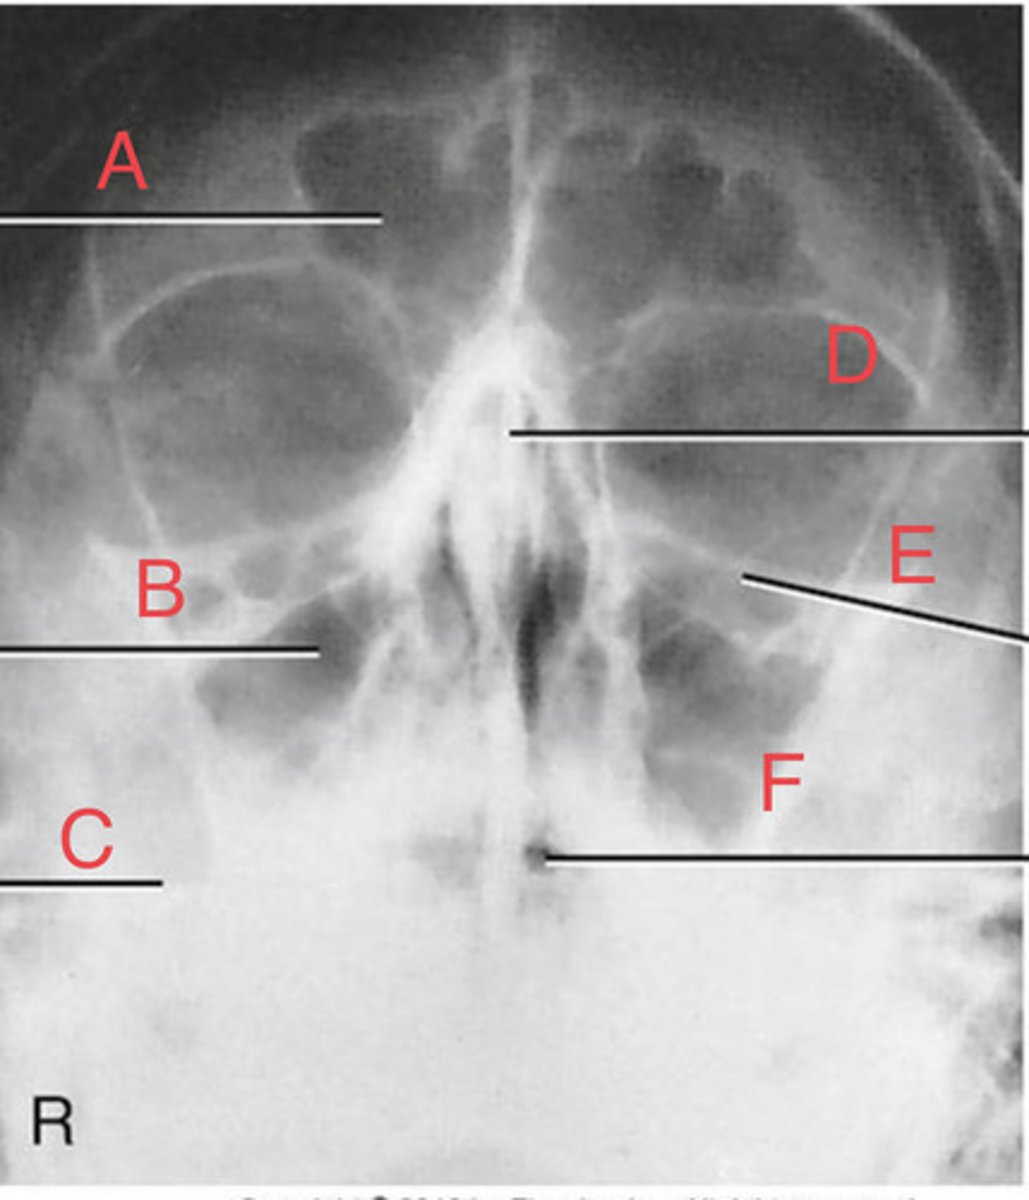

Waters sinus method

What projection?

r. frontal sinus of the frontal bone

A.

R. Maxillary sinus of maxilla

B.

R. petrous ridge of temporal bone

C.

bony nasal septum

D.

L. inferior orbital fissure of sphenoid bone

E.

Sphenoid sinus of sphenoid bone

F.